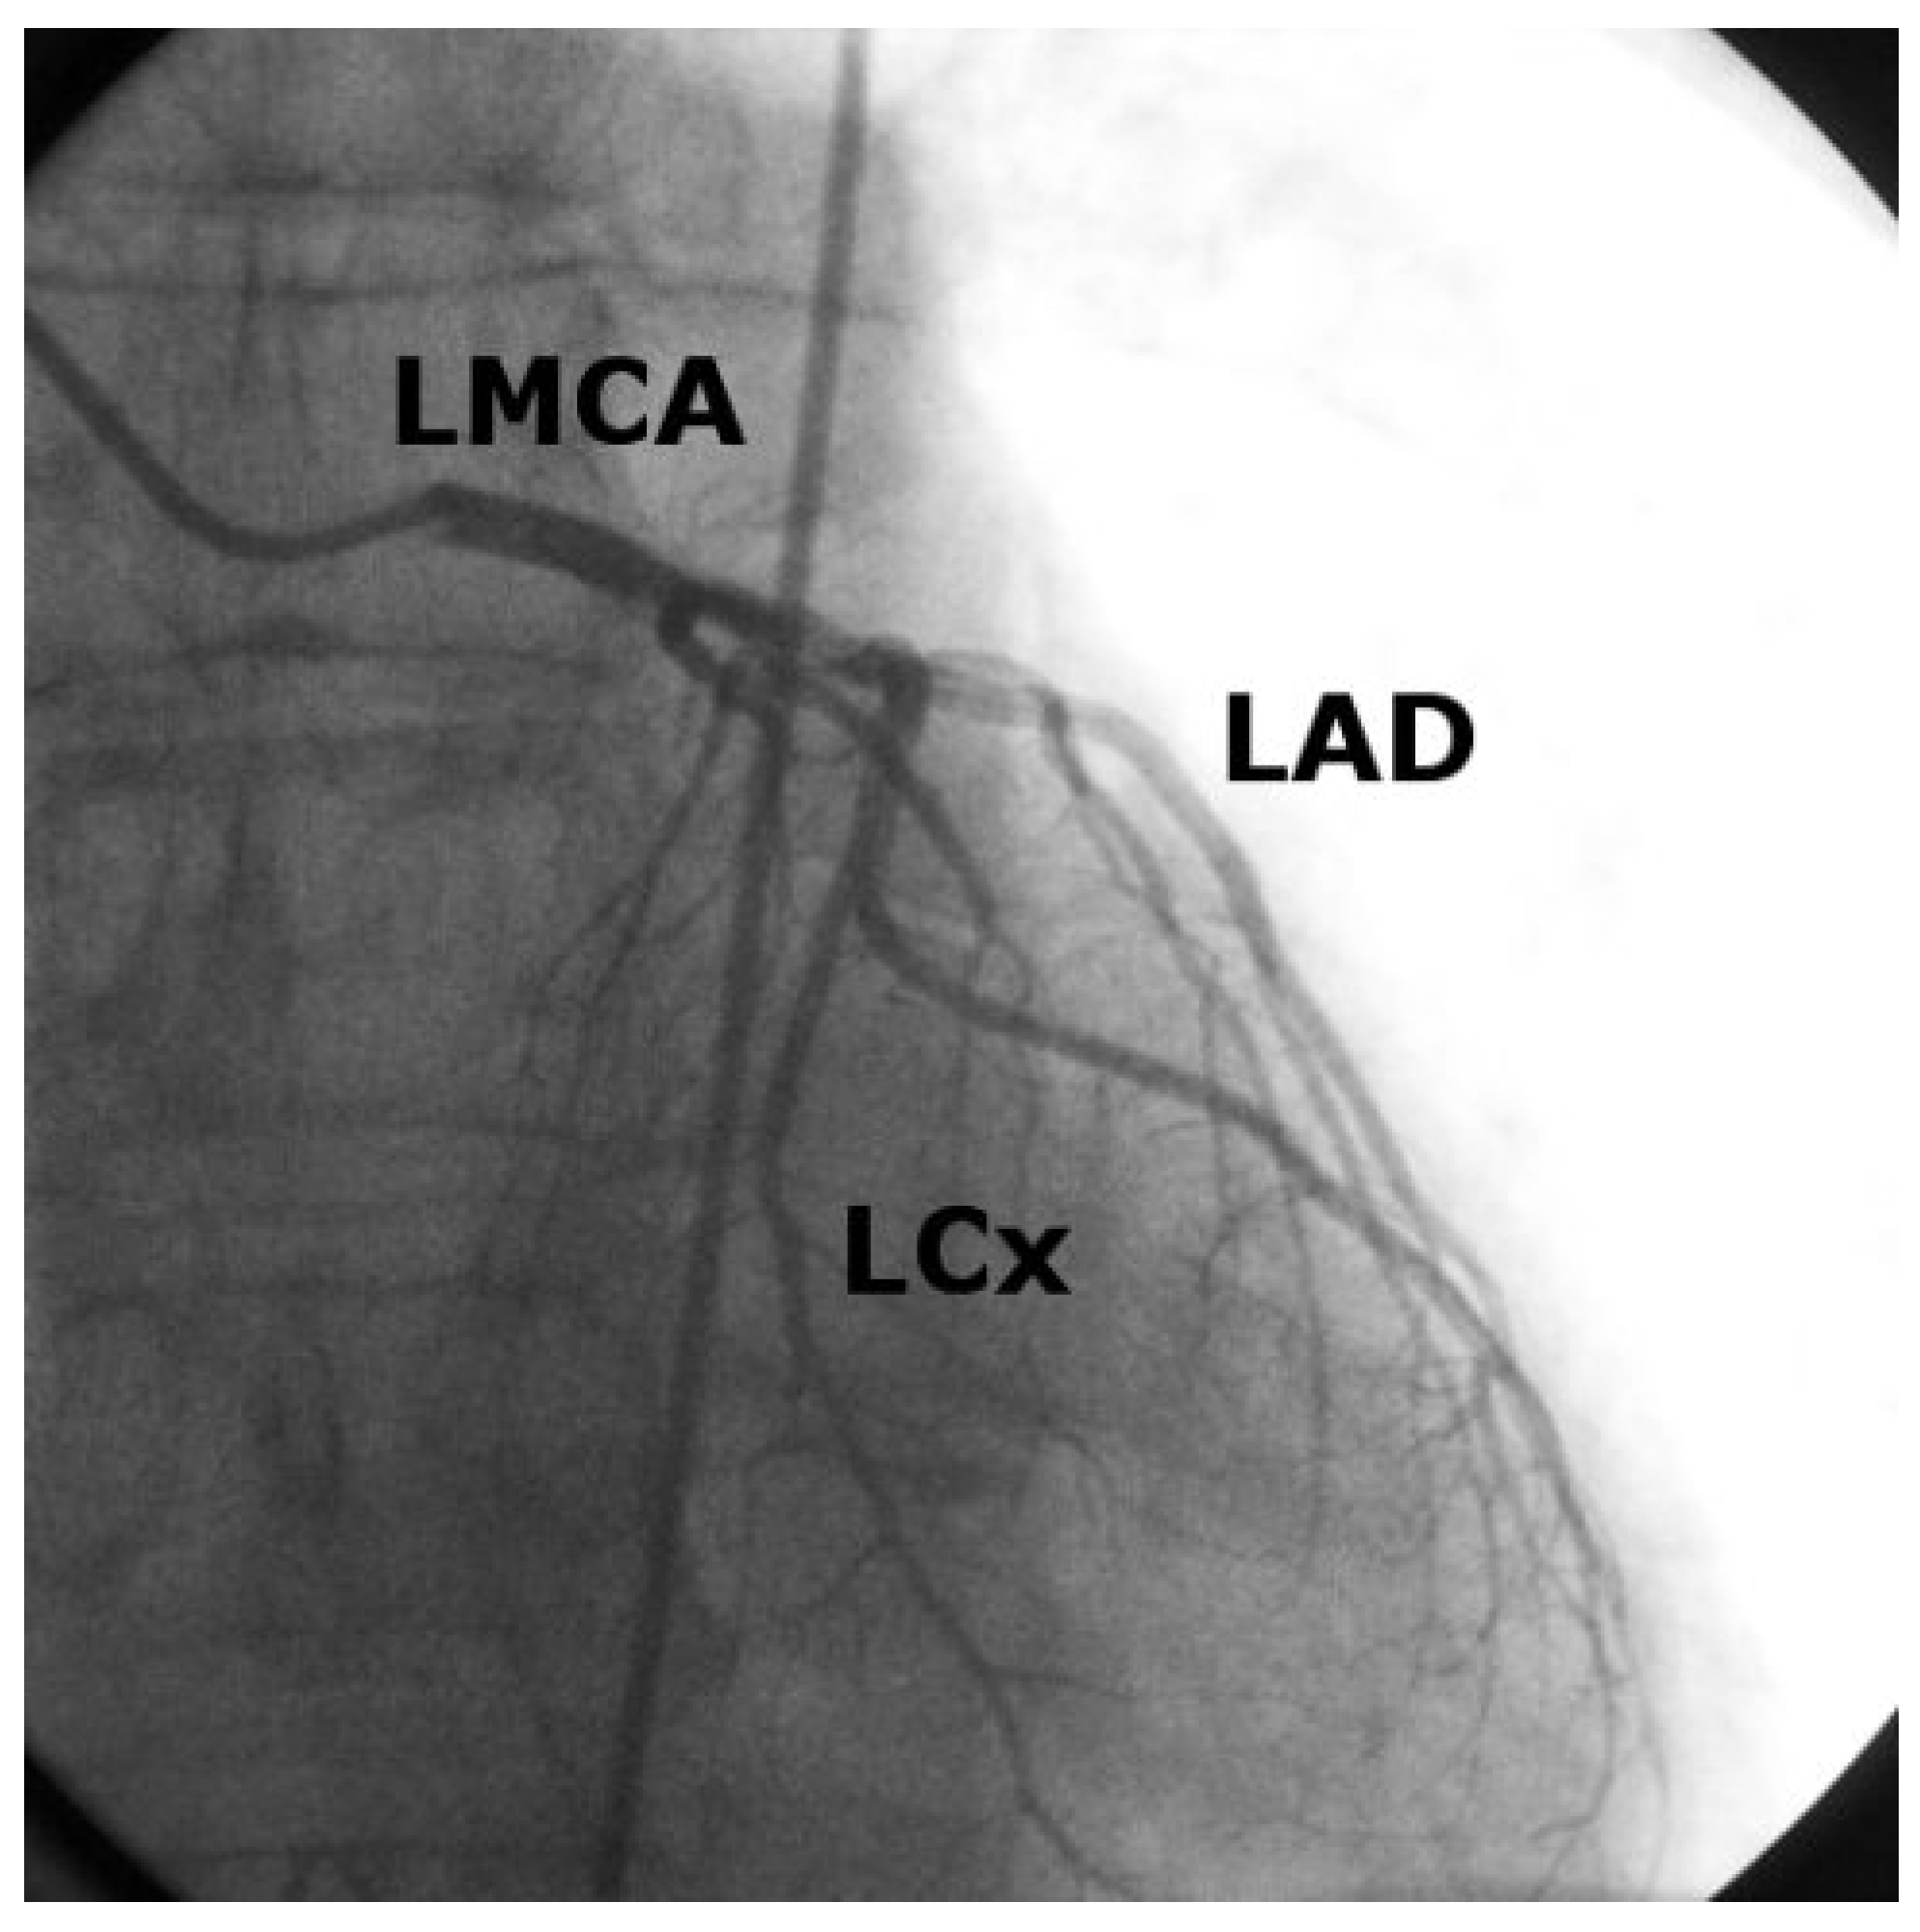

Case 1